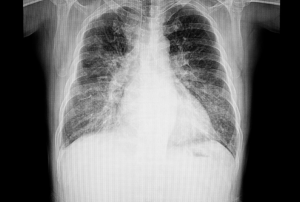

A chest x-ray film of a patient with congestive heart failure